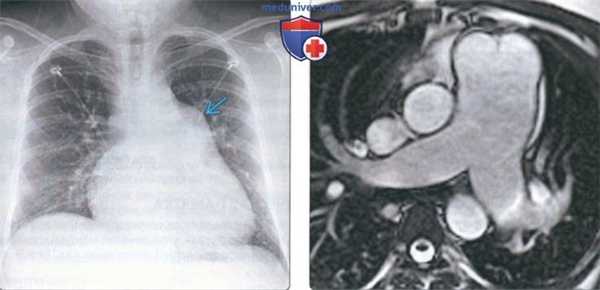

(Слева) На рентгенограмме органов грудной клетки в прямой проекции у молодого пациента с открытым артериальным протоком и синдромом Эйзенменгера определяется расширение легочного ствола и центральных легочных артерий, а также кардиомегалия.

(Справа) На аксиальном скане (SSFP) у этого же пациента определяется выраженное расширение легочного ствола. В норме диаметр нисходящей аорты и легочного ствола обычно приблизительно одинаков. Расширение легочного ствола > 29 мм является признаком легочной гипертензии.